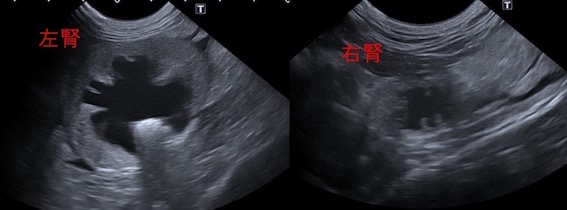

超音波検査画像です。

左腎は重度の腎盂拡張が認められました。

右腎は萎縮しており、腎機能はかなり低下していることが予想されました。